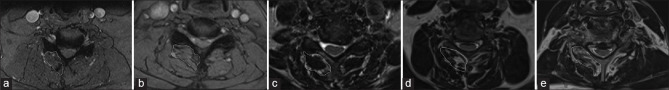

Materials and methods: A retrospective review was conducted on cervical myelopathy patients treated with laminoplasty between January 2019 and January 2022 at a tertiary care center. Inclusion criteria included pre- and 1-year postoperative X-rays and magnetic resonance imaging within 6 months presurgery. PKD was defined as loss of cervical lordosis greater than -10° based on the C2-7 Cobb angle. Fatty infiltration was evaluated using Goutallier classification and voxel quantification.

Results: Among 44 patients, 4 developed PKD. Qualitatively, 32 patients were classified as Goutallier 0-1.5, 6 were Goutallier 1.5-2.5, and 6 Goutallier 2.5-4. There is a significant association between the Goutallier grade and PKD occurrence after 1 year (P = 0.00085). Quantitatively, the average fatty infiltration percentage for the kyphotic patients was 23.3% ± 5.81% versus 13.8% ± 9.83% for nonkyphotic patients. A significant association was found between the percentage of fatty infiltration and the PKD after 1 year (P = 0.045). The optimal fat cutoff between kyphotic and nonkyphotic patients was 23% (P = 0.056).